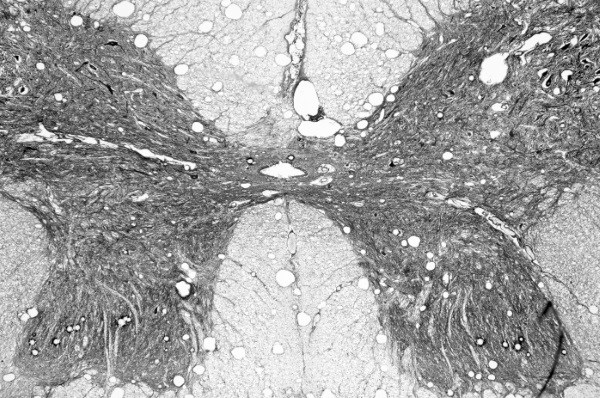

![]() Передние и задние рога серого вещества спинного мозга окружены белым веществом. Белое вещество Белое вещество состоит из пучков миелиновых нервных волокон, которые образуют нервные пути, проходящие вверх и вниз по позвоночнику и соединяющие мозг в обоих направлениях. Восходящие нервные пути направляют сенсорные импульсы в мозг, а нисходящие отправляют двигательные команды в ПНС. Центральный распределитель нервных сигналов Эти волокна нейронов по всей длине спинного мозга объединяются со вставочными нейронами, которые передают сообщения чувствительным или двигательным нейронам. Распознанные организмом ощущения передаются в головной мозг, а эффекторные команды отправляются из мозга в ткани организма. Спинной мозг – это полноценный менеджер среднего звена. Чтобы лишний раз не обращаться к руководству, он сам управляет простыми рефлексами (см. «Рефлексы» на стр. 98–99). Это защищает головной мозг от перегрузки и позволяет ему фокусировать ресурсы на более насущных делах. ![]() Наш спинной мозг отлично поживает внутри костей спины. Анатомия нерва Нерв – это не синоним нейрона, хотя последний и входит в его состав. Нервы состоят из пучков двигательных и чувствительных нейронов, или волокон, а также кровеносных сосудов и соединительной ткани. По своему строению нервы немного похожи на мышцы: они также собираются в пучки, а каждый их внутренний слой выстлан соединительно-тканной прослойкой. Каждое аксональное волокно заключено в слой рыхлой соединительной ткани (эндоневрий). Сами эти волокна объединяются в пучки нервов, и их оборачивает периневрий. Нервный ствол образуют пучки аксональных волокон с кровеносными сосудами, он также покрыт эпиневрием. ![]() Нерв содержит пучки нервных волокон. 43 Соединить центральную нервную систему с остальной частью организма достаточно сложно. Здесь, как и в системе кровообращения, нужна крупная сеть специальных структур, разветвляющихся в каждый сантиметр тела. ПНС делает это с помощью 43 пар нервов. Черепные нервы 12 из 43 пар нервов приходится на черепные нервы. Они отходят от нижней части мозга и иннервируют органы чувств и мышцы головы. Исключение составляет X пара – блуждающий нерв, или вагус, который проходит по телу и соединяет дыхательные пути, сердце и пищеварительную систему. Одни черепные нервы относятся к категории двигательных, другие – чувствительных, а третьи являются и тем, и другим. ![]() Существует 12 пар черепных нервов. Спинно-мозговые нервы 31 пара спинномозговых нервов служит переносчиком как сенсорных, так и моторных сигналов. Эти нервы иннервируют соматические и вегетативные отделы ПНС в областях ниже шеи. Некоторые нервы объединяются, образуя нервную сеть под названием «сплетение». Начиная со второго поясничного нерва и до самого конца позвоночника спинномозговые нервы свободно плавают в СМЖ, образуя пряди, похожие на конский хвост. Их так и называют – конский хвост. ![]() Периферические нервы выходят из спинного мозга. Ветви и корешки Первую часть нерва, выходящего из ЦНС, называют нервным корешком. В основном корешки черепных нервов образуются из ствола головного мозга, за исключением обонятельных и зрительных нервов, которые отходят из головного мозга. Корешки спинномозговых нервов, напротив, отходят от спинного мозга. У них есть двигательные или чувствительные отростки, которые впадают в передние или задние рога серого вещества переднего мозга либо выходят из них. Двигательные (эфферентные) нервы выходят из спинного мозга вертикально – с передней стороны, или антериально. Их чувствительные собратья (афферентные нервы) входят в спинной мозг дорсально – с задней стороны, или постериально. Смешанные спинномозговые нервы появляются, когда вентральные и дорсальные корешки сливаются чуть дальше от спинного мозга. Затем они снова разделяются и образуют ветви, каждая из которых переносит моторные и сенсорные нервные сигналы. Эти нервы продолжают ветвиться, формируя в организме нервную сеть. Ганглии Ганглии – это скопления клеточных тел нейронов, чем-то похожих на ядра в головном мозге. В отличие от мозговых ядер, ганглии рассредоточены по всей площади ПНС. Сенсорные, или корешковые, ганглии располагаются в дорсальных корешках спинномозговых нервов. Вегетативные ганглии (см. «Вегетативные ганглии» на стр. 221) связывают вегетативную и соматическую системы. Для этого они формируют вертикальные цепи, которые с помощью нервных ветвей прикрепляются к спинномозговым нервам. Это автоматика У ПНС есть не только соматическая (телесная) часть, но и вегетативная (автономная), которая помогает телу осуществлять ряд действий (например, дышать) без сознательных усилий с нашей стороны. Вегетативную нервную систему (ВНС) регулирует гипоталамус. ![]() Соматическая часть ПНС состоит из двигательных и чувствительных нервов. Они соединяют головной мозг с органами чувств, которые получают информацию о внешнем мире и позволяют нам осмысленно решать, как лучше отреагировать на происходящее. ВНС состоит из двигательных, или эфферентных, нервов. Обычно эти нервы отходят от спинного мозга, но часть выходит из ствола головного мозга. Эфферентные нервы иннервируют кровеносные сосуды, железы и такие органы, как сердце, легкие, желудок, кишечник, мочевой пузырь и половые органы. Симпатика и парасимпатика Как только гипоталамус получает информацию об изменении, к примеру сердечного ритма или артериального давления, он активирует соответствующие центры в стволе мозга (продолговатый и средний мозг). Мозговые центры стимулируют АНС, чтобы вернуть организм в состояние баланса. В этой обратной цепной реакции задействовано две части АНС – как инь и янь. Симпатическая нервная система готовит нас ко встрече с любыми угрозами и выдает быструю реакцию, помогающую выйти из сложных ситуаций. Парасимпатической нервной системе, наоборот, требуется некоторое время на принятие решений. Можно сказать, что она является стандартным режимом нашего организма, поскольку занимается более рутинными и не угрожающими жизни задачами. Парасимпатика побуждает нас либо «есть и размножаться», либо «отдыхать и переваривать». В реальности отношения между этими двумя системами не столь однозначны. Тем не менее они обе работают на благо баланса и гомеостаза в тех случаях, когда что-то идет не так. |